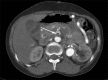

Dacron graft aneurysm with dissection

Dacron grafts have been used as a conduit for large caliber arteries for many years successfully. However, these grafts can undergo complications such as aneurysm formation, rupture, and failure. Evaluation of these complications are of paramount importance because of its tendency to rupture and cause death. Imaging plays an important role in identifying and monitoring of these complications, and also provides a road map to the vascular surgeons for early intervention and revascularization.